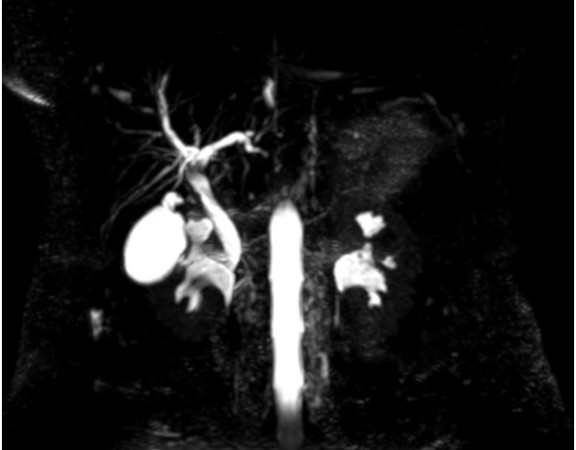

A 39 years old female was admitted with complaints of recurrent pain abdomen of many years duration. She gave a history of jaundice in the past […]